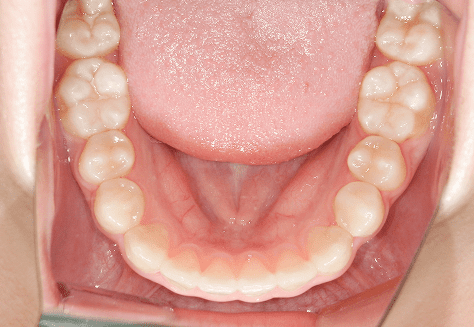

M.U

治療前

治療後

主訴

下の歯が特にガタガタなのが気になる。上の前歯が1本反対になっている。

診断

下顎前突・叢生・反対咬合

年齢/性別

20代/男性

抜歯部位

非抜歯

使用装置

上下インビザライン(PBM使用)

保定装置

ビベラリテーナー

診察料金

5,500円×16回

治療期間

1年7カ月